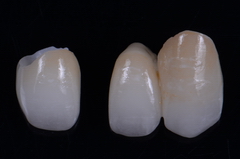

オールセラミックスを作製しました。

オールセラミックスを作製しました。

完成したラミネートベニア

完成したラミネートベニア